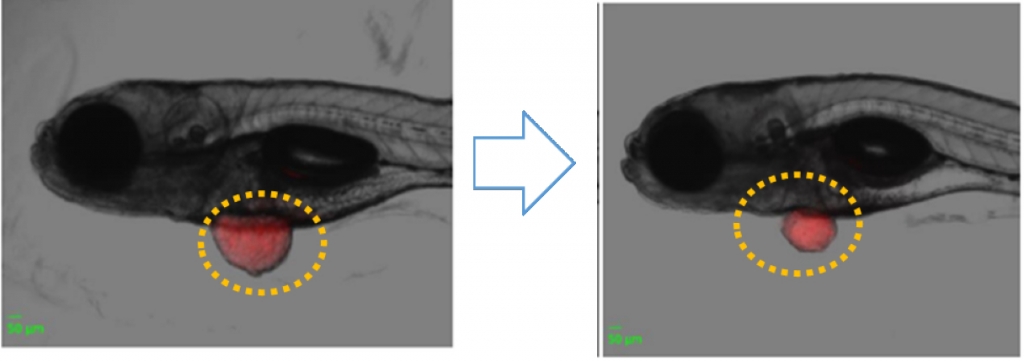

쿼럼바이오는 제브라피시에 암세포를 이식한 뒤 각각 QAL-333과 플루오로우라실(FOLFIRI)을 투여했다. QAL-333을 투여한 제브라피시는 암세포 크기가 유의미하게 감소한 결과를 보였다.

회사 관계자는 " 제브라피시를 이용한 전이성 대장암의 억제 실험에서 효과 좋은 병용 항암요법으로 알려진 플루오로우라실과 대등한 효과를 보였다"고 말했다.